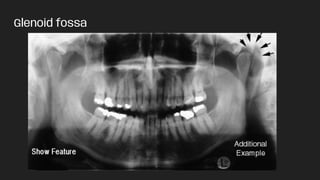

MIDFACIAL REGION LANDMARKS

Radiopaque features:

● Glenoid fossa

Glenoid fossa